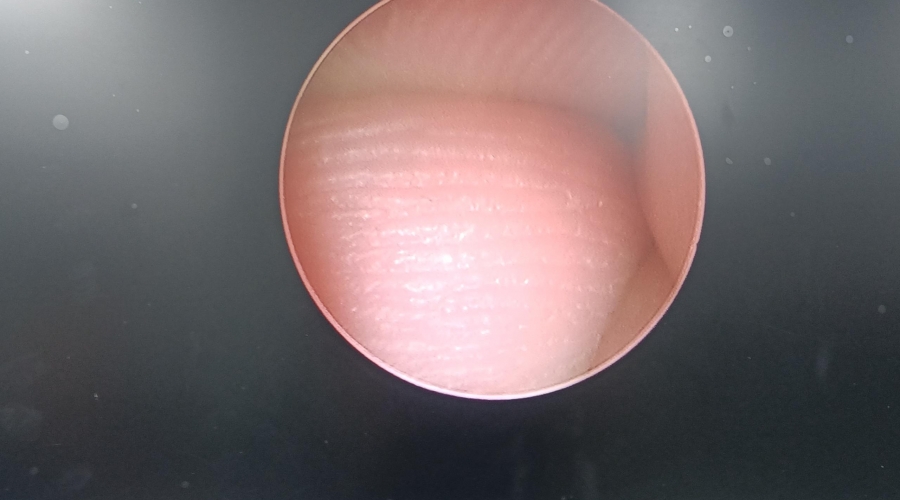

以下為維修案例分析及故障實(shí)拍:

故障內(nèi)容圖像模糊,棒透鏡破碎。

維修方案更換棒透鏡 ,校對圖像,內(nèi)窺鏡抗震蕩抗沖擊性能測試,內(nèi)窺鏡密封性性能檢測;內(nèi)窺鏡抗震蕩性能測試,內(nèi)窺鏡冷熱沖擊性能檢測。